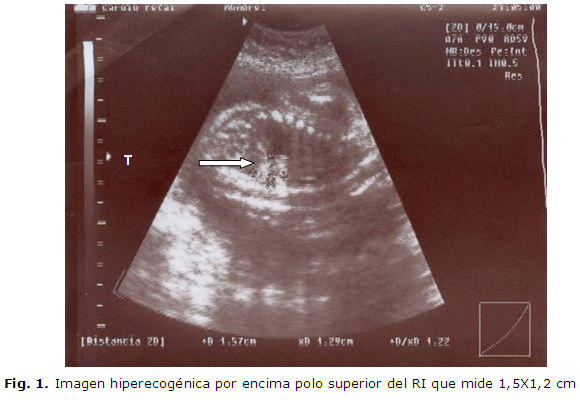

El día 24 de mayo acude para que se le realice dicho examen, y se encuentran ambos ecocardiograma fetales normales, pero se decide realizar ecografía completa, donde se encuentra en el primer gemelar una tumoración hiperecogénica de forma triangular que mide 15 X 12 mm por encima del polo superior del riñón izquierdo y por debajo del diafragma. El resto del examen de ese feto era normal. (Figura 1 y Figura 2).

En el otro feto se encontró un quiste del polo superior del riñón derecho sin otras alteraciones. Dado los hallazgos ecográficos se planteó en el primer feto que la imagen tumoral observada podía estar en relación con un tumor sólido de suprarrenal (neuroblastoma), y como diagnóstico diferencial un secuestro extralobar, que son los más frecuentes precisamente en la parte subdiafragmática izquierda.